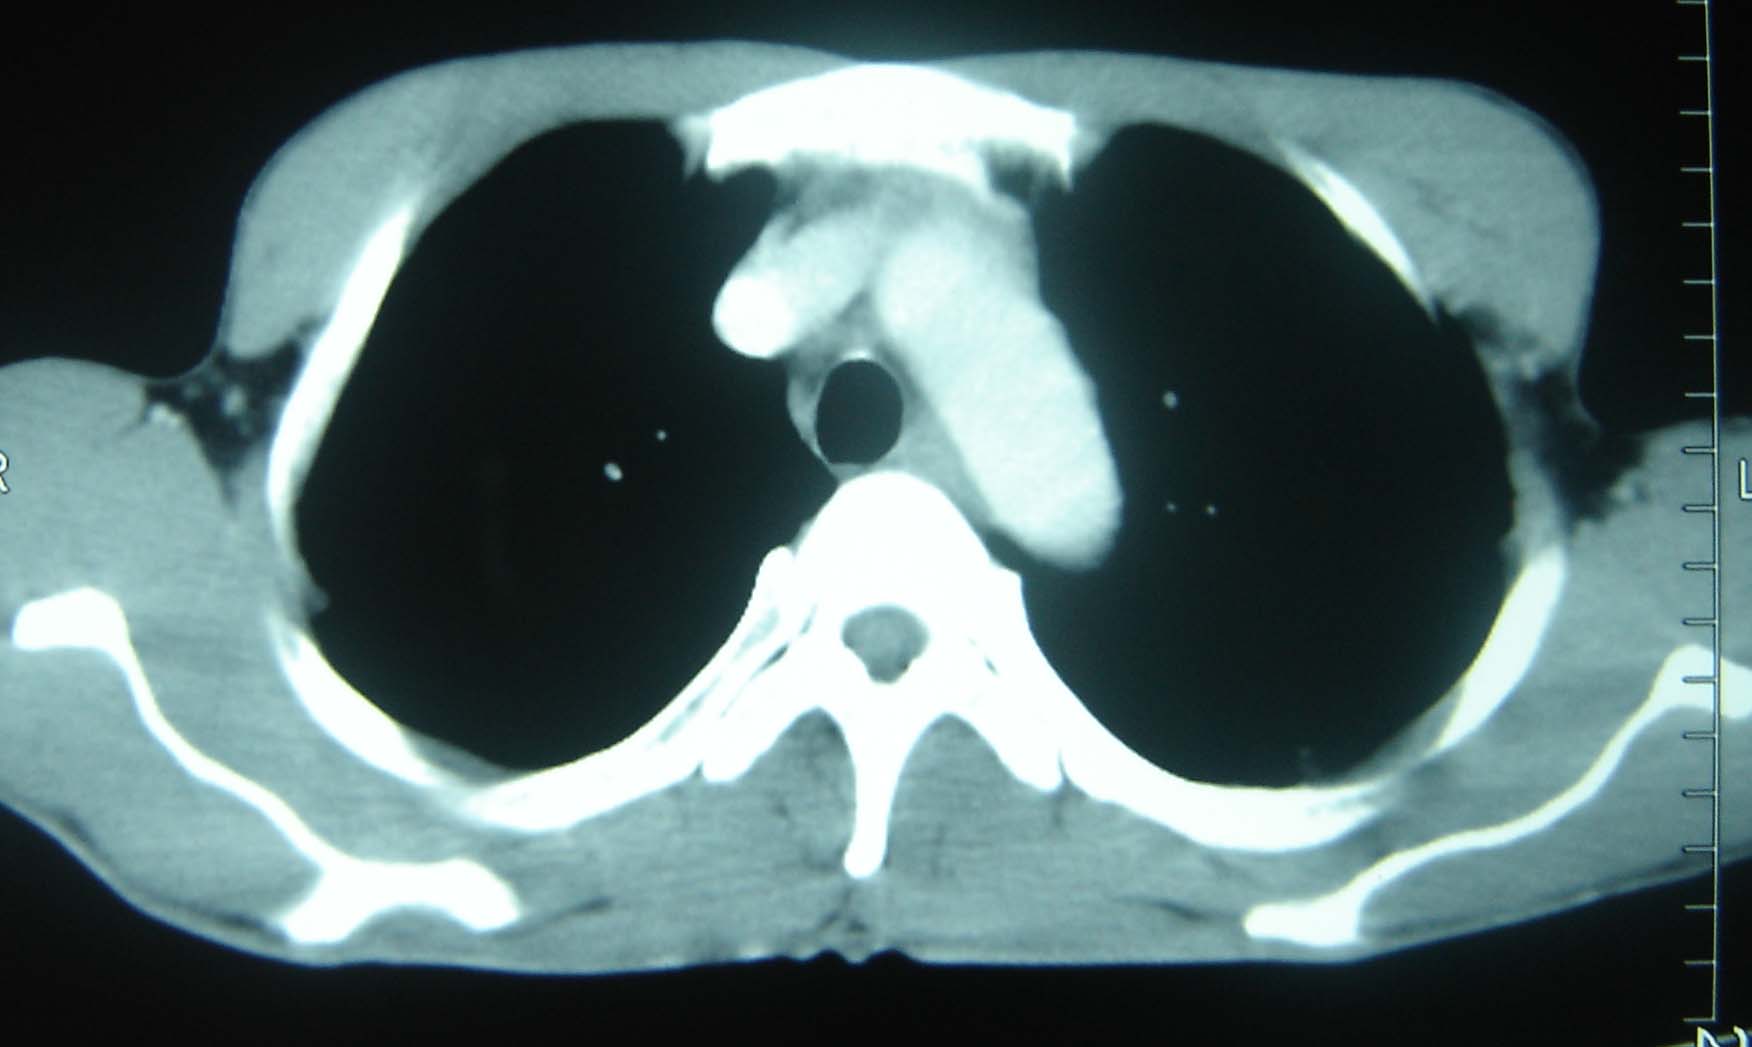

男 、43岁,咳嗽胸痛,装修工,平时接触粉尘较多,有吸烟史10多年,纤维支气管镜检查未发现异常,胃镜、腹部b超检查亦未发现异常,颈部淋巴结活检未发现肿瘤细胞。

不能排除转移,如果不能找到原发灶,只有短期随访。

结节病?转移瘤?

结节病。

转移瘤?

转移

1)考虑双肺及胸膜多发性转移瘤。2)肺气肿。

双肺结节病。